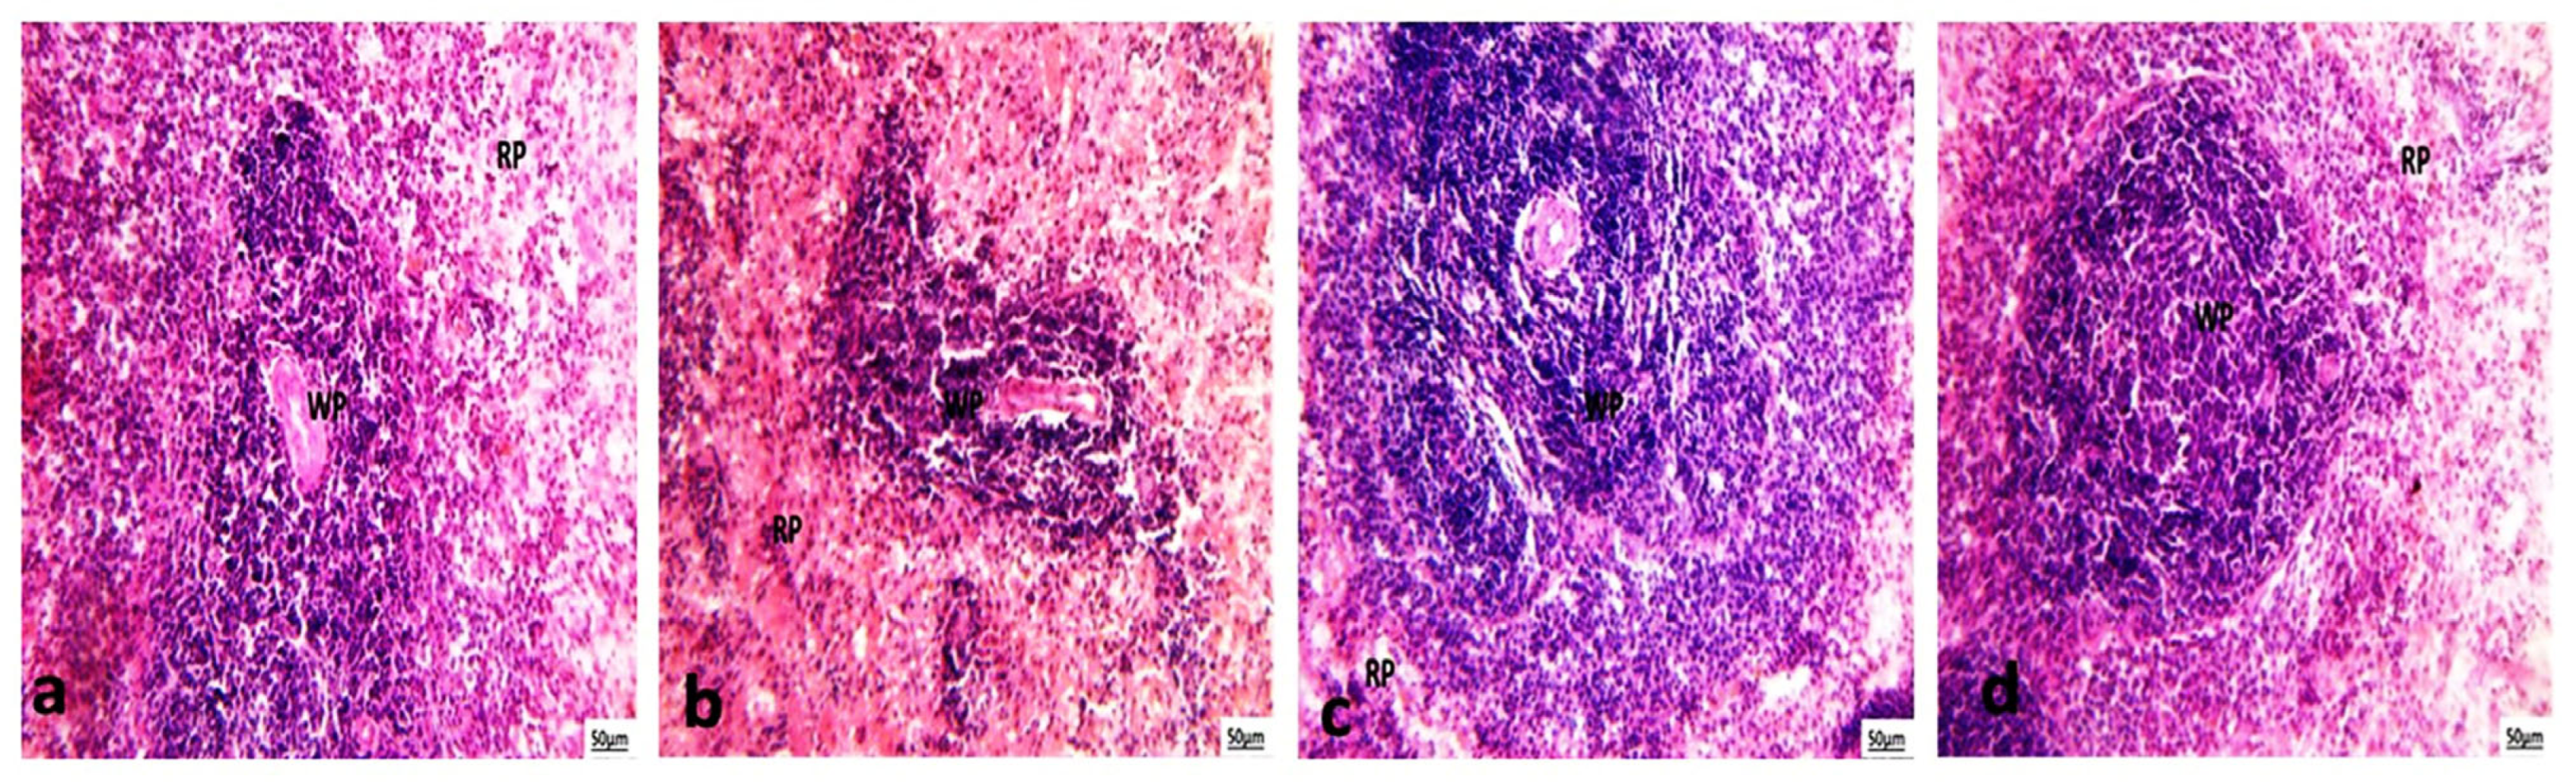

3.5.3. Histological Examination of Spleen

3.6. Immunohistochemical Expression Nrf2 of Liver and Kidney